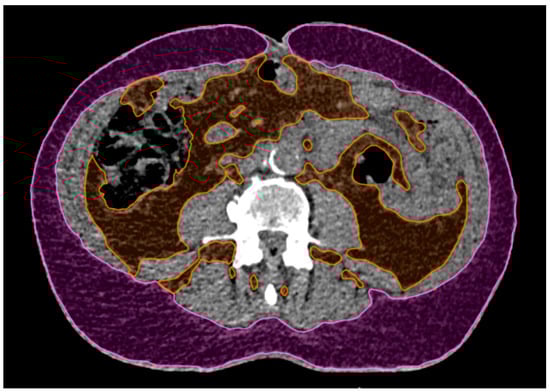

The adipose tissue was measured on a single CT slice at the level of L4. The tissue in the range of −20 to −150 Hounsfield units was delineated and the total adipose tissue (TAT) was separated into visceral (VAT) and subcutaneous (SAT) adipose tissue, as shown in Figure 5. The total slice surface area was also measured. The percentage of total (TAT%), visceral (VAT%) and subcutaneous (SAT%) adipose tissue was determined. For the body mass index, the patient data collected at the time of 4DCT acquisition were used.

Figure 5.

An example of subcutaneous (magenta) and visceral (orange) adipose tissue delineated on a single CT slice at the level of L4. Areas of the delineated surfaces relative to the total slice surface area were used to compute the subcutaneous, visceral and total adipose tissue percentages (SAT%, VAT% and TAT%, respectively).